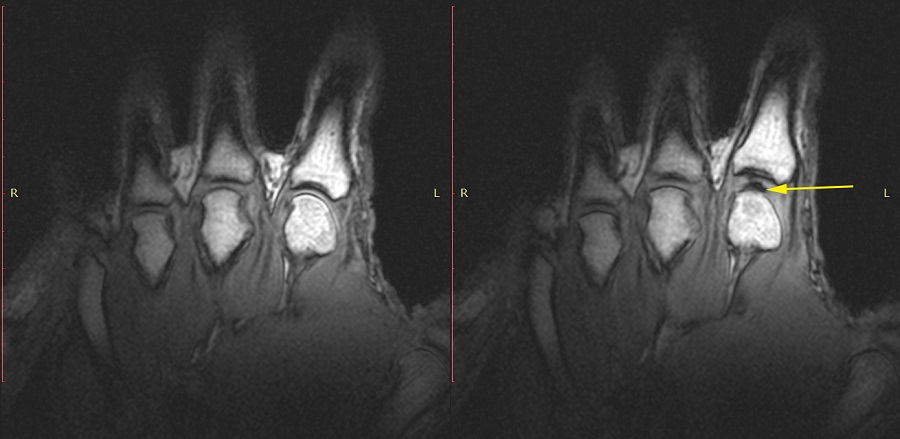

В 2015 году загадка, казалось, была разгадана: используя магнитно-резонансную томографию, канадские ученые из Университета Альберты заглянули внутрь хрустящего сустава и убедились в том, что звук возникает не тогда, когда пузырьки газа лопаются, а в момент их появления. Они связали это с резким перепадом давления в суставе, возникающим вследствие очень быстрого формирования газового пузыря.

Идея перепроверить результаты канадцев пришла в голову одному из студентов Бараката и соавтору работы, опубликованной на этой неделе в журнале Scientific Reports. Прямое наблюдение за тем, что происходит в суставе, нельзя использовать как доказательство причинно-следственной связи между событием и звуком из-за низкого временного разрешения магнитно-резонансных томографов. Так решили ученые — и вместо того, чтобы разглядывать снимки суставов, создали математическую модель заполненной жидкостью суставной сумки.